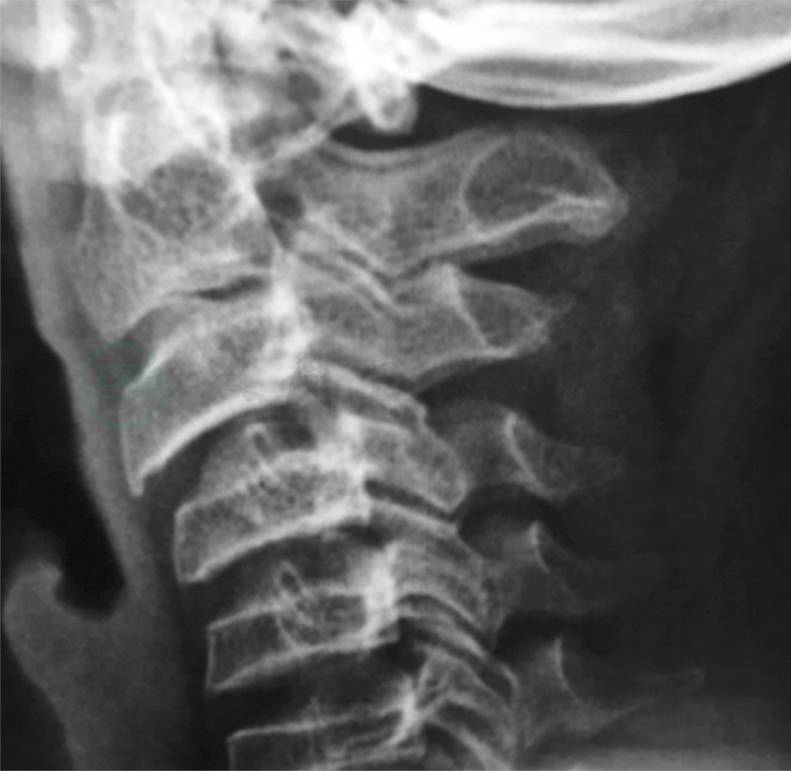

6.颈椎侧位片(图3)多发椎体高度变扁。

图3 颈椎侧位片